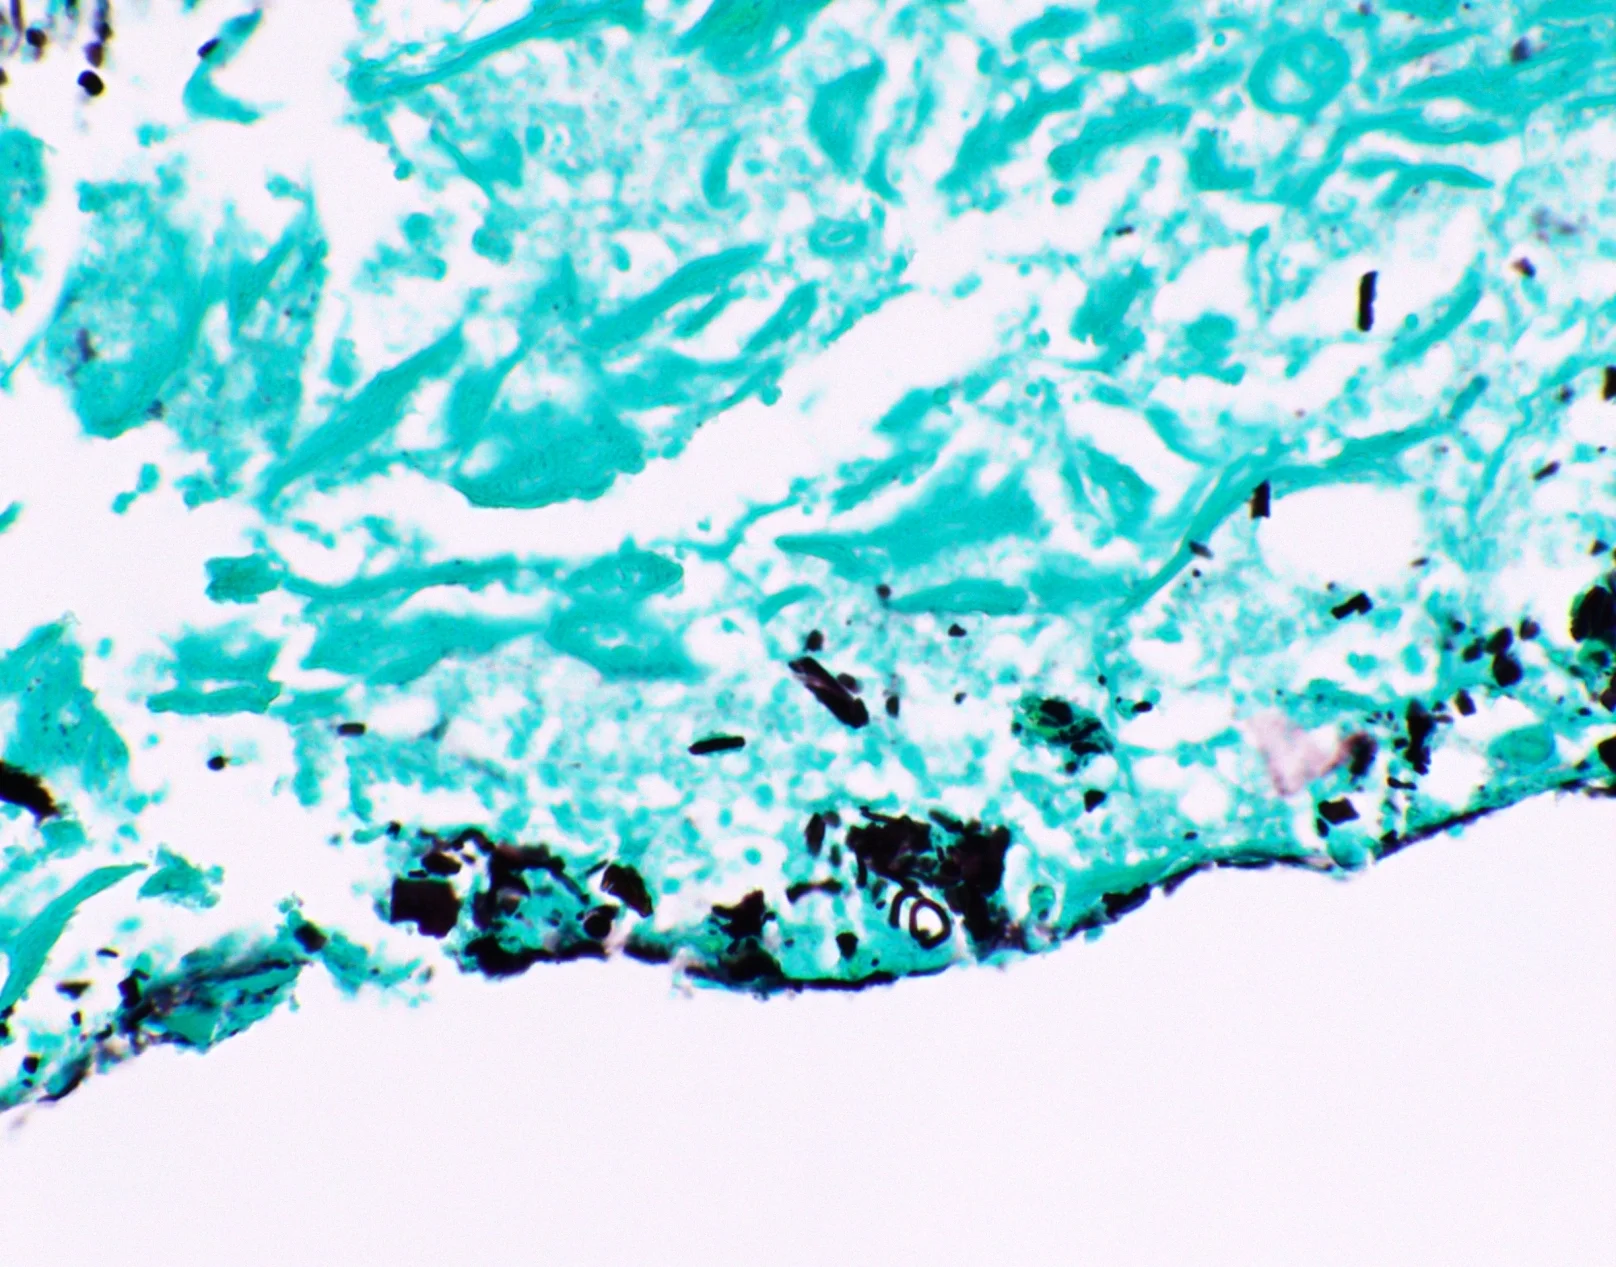

نتایج رنگ آمیزی گوموری متنامین سیلور

- رنگ سیاه برای Pneumocystis jirevoci و Histoplasma spp دیده میشود.

- میسلیومها و هیفها در داخل بدن رنگ صورتی مایل به قرمز به خود میگیرند.

- سبز روشن به پس زمینه نفوذ کرده و لکه سبز کم رنگی به جا میگذارد.

| قارچ، پنوموسیستیس کارنی، هیستوپلاسما | سیاه |

| قسمتهای داخلی میسلیومها و هیفها | صورتی مایل به قرمز |

| لیشمانیا ، توکسوپلاسما | رنگ آمیزی منفی |

| موسین | خاکستری تیره |

| پس زمینه | سبز کم رنگ |

با توجه به فرآیند کاهش محلول نیترات نقره، گونههای قارچ سیاه رنگ میشوند. پس از احیا، محلول نیترات نقره یونهای نقره سیاه رنگ تولید میکند که سلولهای قارچ را سیاه میکند.

به دلیل تبدیل نیترات نقره به یون نقره، میسلیوم و هیف قارچ به رنگ صورتی مایل به قرمز رنگ میگیرد، در حالی که موسین به رنگ خاکستری تیره میشود. استفاده از گرین لایت باعث میشود پس زمینه سبز مایل به آبی به نظر برسد.